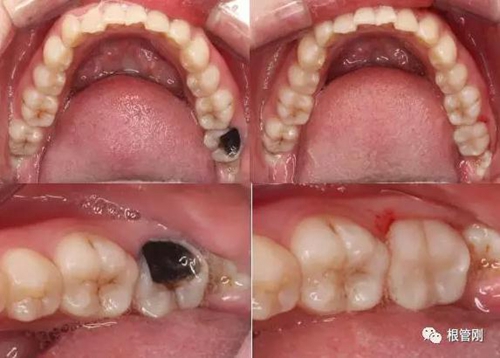

這是一顆嚴(yán)重的蛀牙,顏色發(fā)黑,牙齒的一半已經(jīng)崩解,看到此情此景,也許很多人會(huì)想它的神經(jīng)肯定死掉了吧?它還有救嗎?應(yīng)該會(huì)做根管治療+牙冠修復(fù)吧?

3.jpg

4.jpg

經(jīng)細(xì)致的詢問病史(有沒有自發(fā)痛,冷熱刺激敏感等)、仔細(xì)的檢查(包括探診,冷診,熱診,叩診以及牙片的檢查不可缺少),綜合各種信息判斷,得出準(zhǔn)確的診斷為深齲,在與患者溝通,患者同意直接樹脂修復(fù)!